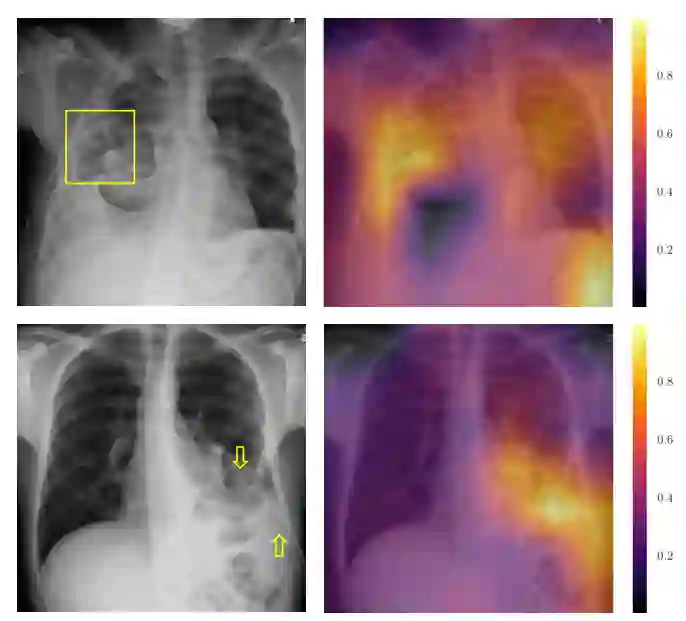

图 5.5:两个示例图像的 Grad-CAM 结果。在顶行中,气胸的位置用黄色框标记。如旁边的 Grad-CAM 图像所示,模型对预测的最高激活位于正确区域内。第二行显示了一个负例,其中负责最终预测“气胸”的最高激活位于排水管。排水管标有黄色箭头。这表明经过训练的卷积神经网络将引流检测为“气胸”的主要特征。